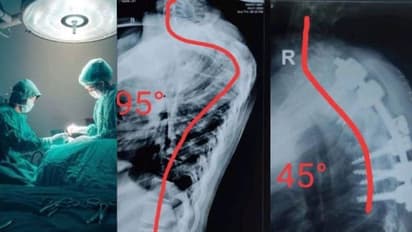

രാജസ്ഥാന് സ്വദേശിനിയായ പന്ത്രണ്ടുകാരിയുടെ നട്ടെല്ലിന്റെ വളവ് അപൂര്വ ശസ്ത്രക്രിയയിലൂടെ നേരെയാക്കി. നട്ടെല്ല് വളഞ്ഞതിനെ തുടര്ന്ന് നടക്കാന് ബുദ്ധിമുട്ട് നേരിട്ടിരുന്ന പെണ്കുട്ടിക്കാണ് അഹമ്മദാബാദിലെ സിവില് ആശുപത്രിയില് ശസ്ത്രക്രിയ നടത്തിയത്. ശസ്ത്രക്രിയ വിജയകരമായിരുന്നുവെന്ന് ഡോക്ടര്മാര് അറിയിച്ചു. കുട്ടിക്ക് ഉടനെ തന്നെ നടക്കാന് സാധിക്കുമെന്ന് ഡോക്ടര്മാര് പ്രതീക്ഷ പ്രകടിപ്പിക്കുകയും ചെയ്തു.

പെണ്കുട്ടിക്ക് അഞ്ച് വയസ്സുള്ളപ്പോള് മുതല് നട്ടെല്ലിന് പ്രശ്നം ഉണ്ടായിരുന്നു. അസ്ഥികളുടെ അമിതമായ വളര്ച്ചയായിരുന്നു പ്രശ്നം. ഇത് ശസ്ത്രക്രിയയിലൂടെ പരിഹരിച്ചു. എന്നാല് വേദന മാറി സാധാരണ ജീവിതത്തിലേക്ക് തിരിച്ചുവന്ന പെണ്കുട്ടിക്ക് വര്ഷങ്ങള്ക്ക് മുന്പ് തന്നെ നട്ടെല്ല് വളയുന്ന സ്ഥിതി ആരംഭിച്ചിരുന്നു. ഏഴുവര്ഷം കൊണ്ട് നട്ടെല്ല് 95 ഡിഗ്രി വരെ വളഞ്ഞ സ്ഥിതിയായി.

കഴിഞ്ഞ ആറുമാസമായി നടക്കാന് പോലും കഴിയാത്ത അവസ്ഥയിലായിരുന്നു പെണ്കുട്ടി. വിവിധ ആശുപത്രികളില് ചികിത്സ തേടി പോയതിന് ശേഷമാണ് അഹമ്മദാബാദില് എത്തിയത്. രാജസ്ഥാനിലെ ജോദ്പൂര് സ്വദേശിനിയാണ് പെണ്കുട്ടി.